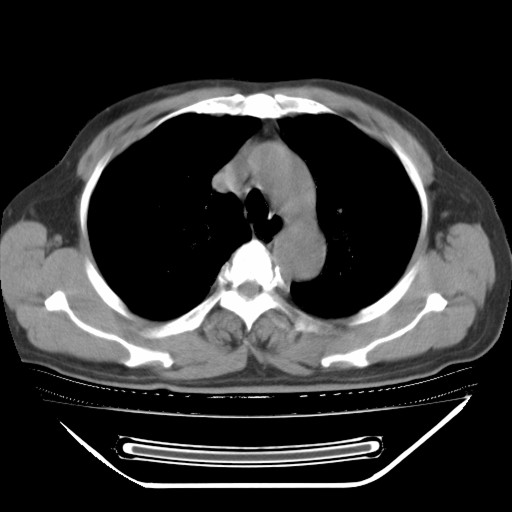

以下是引用hhcckk在2009-5-29 10:34:00的发言:[br]左下肺片絮状边缘模糊影,考虑感染,建议治疗后复查[br]